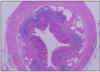

GI TRACT LAYERS (x4)

- mucosa - innermost. epithelium (folded), connective tissue (lamina propria - w/ lymphoid tissue), smooth muscle ring (muscularis mucosa)

- sub-mucosa - loose connective tissue, glands and lymphoid tissue, many blood vessels, meissner’s plexus (enteric nervous sytem)

- external muscle coat (muscularis externa)- 2 layers of smooth muscle - persistalis -auerbach’s plexus (enteric nervous system)

- serosa - simple squamous epithelium

OSEOPHAGUS

mucosa:

- SSNKE

- thin lamina propria

- narrow muscularis mucosa (thicker @ gastric end)

below diaphragm:

- simple columnar epithelium (same as gastric region of stomach)

- site of pathological change - Barrett’s oesophagus!

sub-mucosa: sero-mucous glands (lubrication), large thin-walled veins (@ distal end - oesophageal variscosities)

muscularis externa:

upper 1/3 = skeletal / middle 1/3 = mixed / lower 1/3 = smooth